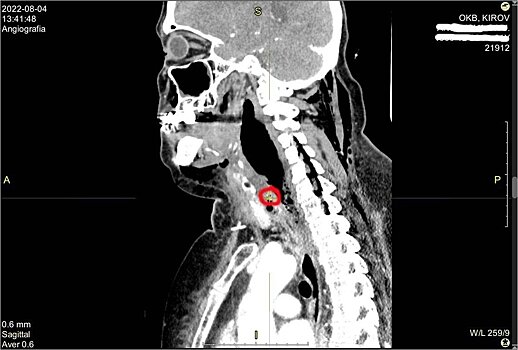

В областную больницу пациентка поступила в тяжелом состоянии с сильнейшим обезвоживанием и интоксикацией. При проведении компьютерной томографии было обнаружено инородное тело шейного отдела пищевода (рыбная кость) и флегмона шеи верхнего средостения. Гнойное воспаление тканей опустилось вниз - в полость между лёгким и сердцем, развился передний медиастинит.